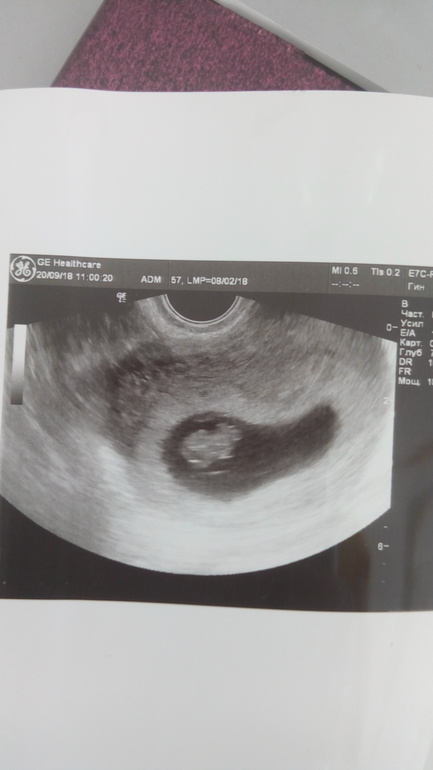

СамочувствиеВчера снова увиделись с крохой. Деть почти 2 см, моторчик работает 170 уд/мин. Врач сказал, что матка в тонусе, но я думаю, что тонус был только на приеме у врача, в кабинете было холодно, мне страшно +усталость и тошнота, я чувствовала как у меня все внутри прям скручивается.

Моя такая в 7,5 была